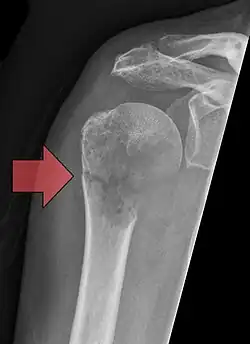

Osteolytische Knochenmetastase im zweiten Halswirbelknochen (Axis) eines metastasierten Prostatakarzinoms -

Osteoplastische Knochenmetastase eines metastasierten Prostata-Karzinoms im Hüftgelenk -